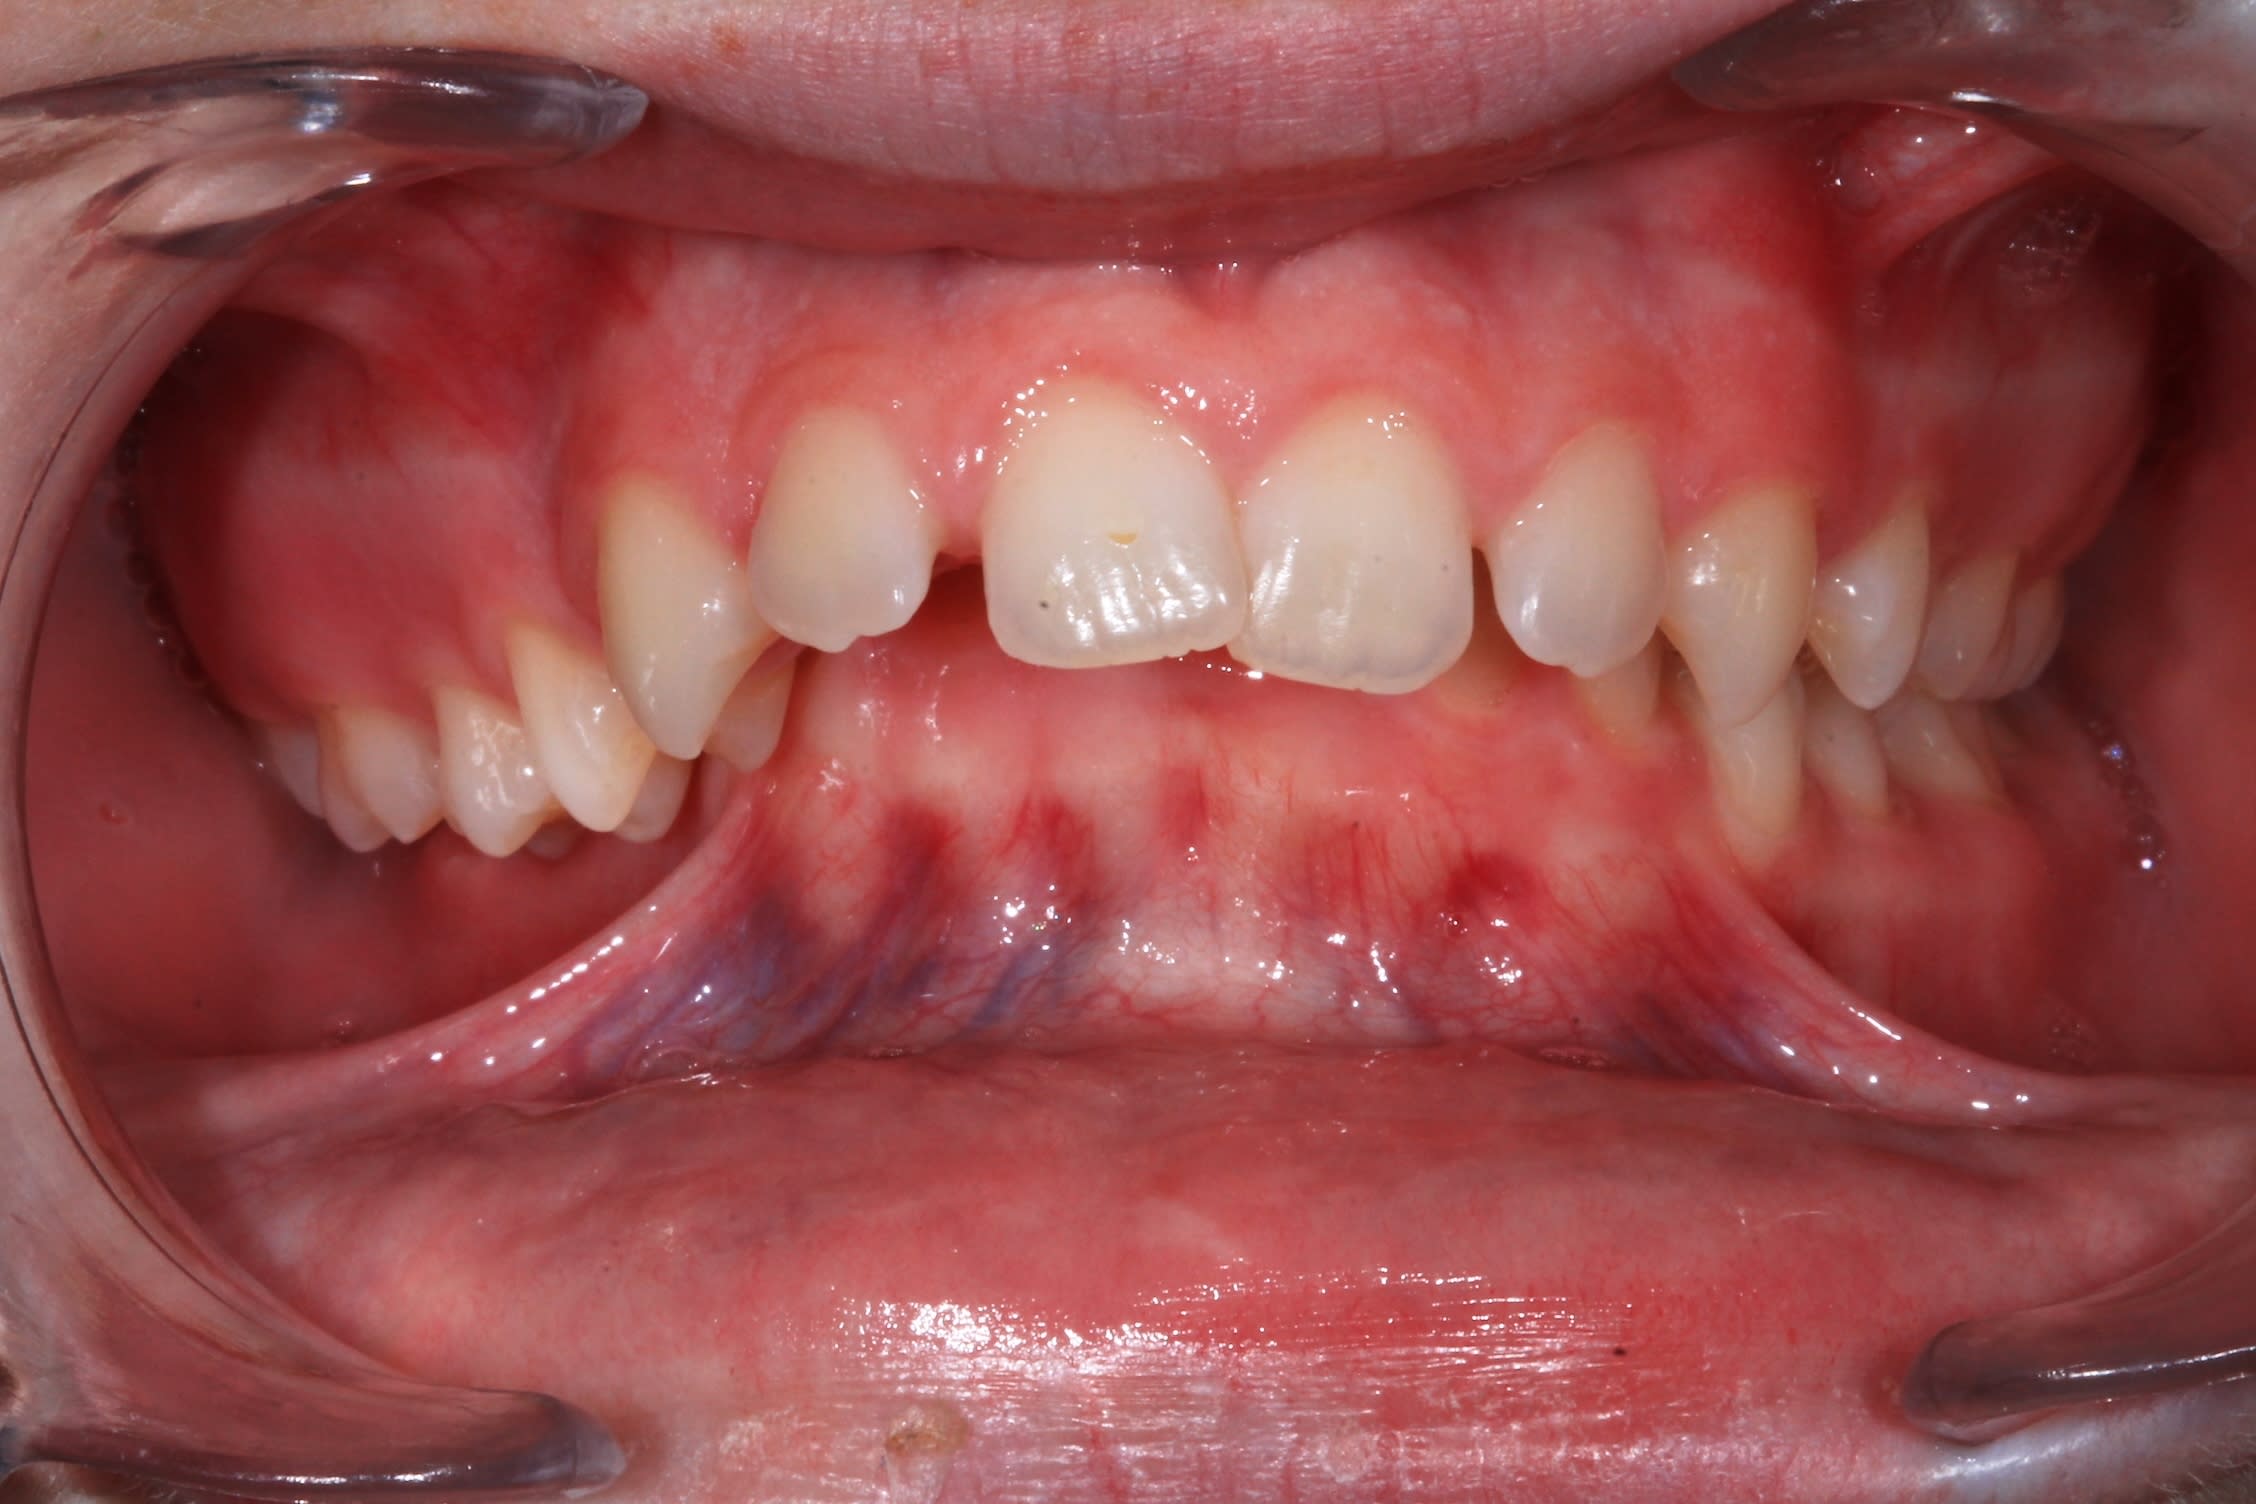

J'ai utilisé parfois les vis façon Chang , notamment pour ce cas de "severe cisor cross bite ", qui ressemble beaucoup a un cas de Chang, que tu as du déjà voir sur sa chaine youtube.

Img 2871 2 urztny - Eugenol

Nov 2018 171 2 kysopg - Eugenol

Jeff très jolie cas! Tu as un canting au maxillaire. Extrusion du quadrant 1. Comment tu as fini ce cas ? j’ai un cas dans le même style que je suis entrain de traiter.